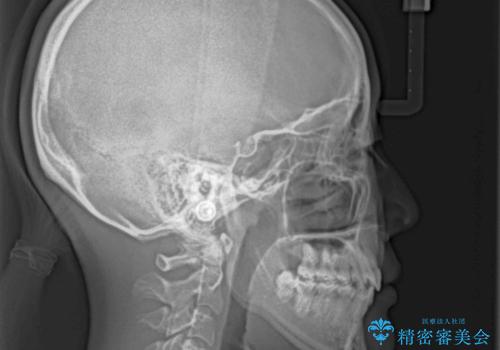

上顎骨幅が狭い 急速拡大装置を併用した抜歯矯正

検査を行った結果、上顎骨の横幅が相対的に狭いことが分かり、叢生が強いことから、急速拡大装置にて上顎骨を側方に拡大することで、叢生の解消と奥歯の咬み合わせ改善を図ることとしました。

急速拡大後、歯列はきれいに並んだのですが、口元が出っ歯になってしまったため、速やかに抜歯を行い、治療期間がいたずらに遅延することのないようにしました。